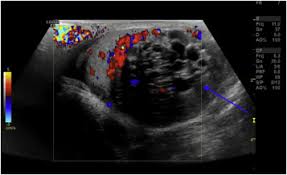

You're right to be concerned. If your doctor orders a computerized tomography scan, you'll be preparing to undergo a ct scan. What you should know before your ct scan we may earn commission from links on this page, but we only recommend products we back. This diagnostic tool is used in many different medical situations, as it gives doctors a way to visualize the body internally to determine the e. A shoulder ct scan will help your doctor see the bones and soft tissues in the shoulder in order to detect abnormalities, such as blood clots or fractures. Optimal Layanan Ct Scan 128 Slice Rsudam Lampung Mampu Periksa 15 Orang Sehari from lampungpro.co Learn about when a ct scan is used for pe, how it works, what it looks like, and more. If a doctor suspects you may have a pulmon. If your doctor orders a computerized tomography scan, yo...